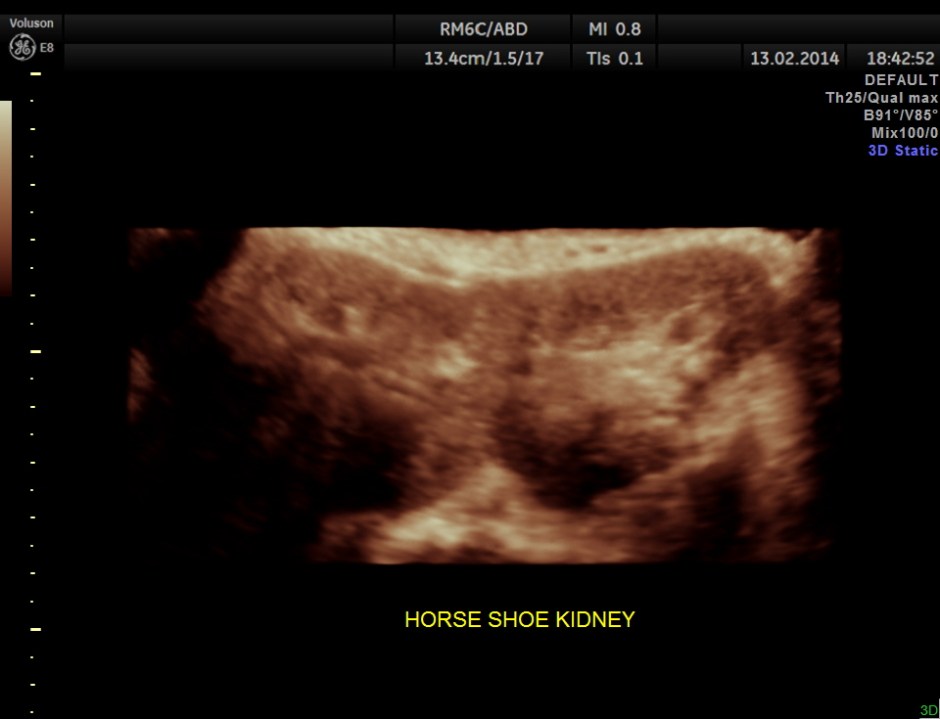

The following are the pictures of the kidney , which show the congenital horse shoe kidneys , placed ectopically in the pelvis. He had no urinary symptoms or low back ache at any time .

some of the reconstructed images are given below.

In this disorder, the patient’s kidneys fuse together to form a horseshoe-shape during development in the womb. The fused part is the isthmus of the horseshoe kidney.

Imaging Findings : The 2 kidneys on opposite sides of the body with the lower poles fused in midline Midline or symmetrical fusion (90% of cases) May be missed on US, therefore pay careful attention to identification of lower poles of kidneys. Renal long axis medially orientated Lower poles with curved configuration, elongation and poorly-defined Isthmus crosses midline anterior to spine and great vessels US for diagnosis in utero IVP followed by CT or scintigraphy for pre-operative assessment

The lower poles of these kidneys fuse in the midline anterior to the aorta and spine. The isthmus is usually located at L4/5 level between the aorta and IMA.